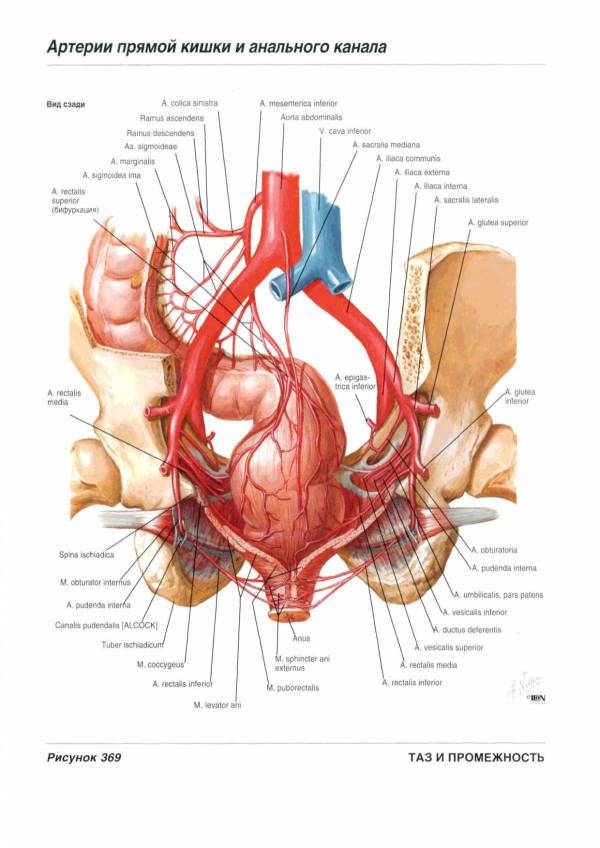

Анатомия малого таза: детальные схемы и изображения